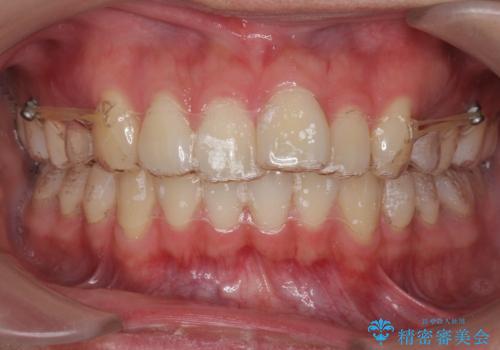

- 出っ歯を主訴に来院。

上の小臼歯を2本抜歯しています。

そのかわり、上の親知らずを生かしており、歯の本数は減っていません。

矯正用ミニスクリューを使用しています(インプラント矯正)。

奥歯の歯ならびのずれが大きく、親知らずを抜いてすべて後ろに下げるか、手前の歯を抜いて前歯を下げるかの2択でした。

時間はかかりましたがしっかり前歯を下げて治療しています。